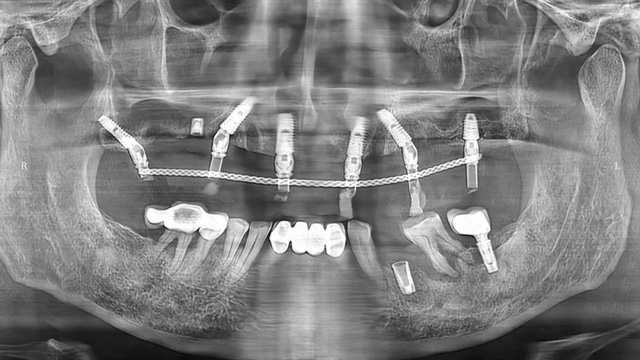

吳叔叔當時的口腔情況

“上面種了4顆,斷了兩顆,脫落1顆,只有1顆能用,下面有一顆牙冠脫落,另一顆有種植體周圍炎,有明顯的骨吸收。”吳叔叔剩下的天然牙也不好,做了幾處修復,之前的牙冠修復用的都是烤瓷牙,有好幾顆磨損嚴重露出了金屬。由于存在缺牙、不良修復體等情況,口腔整體咬合紊亂,進食很困難。

治療前口腔全景片